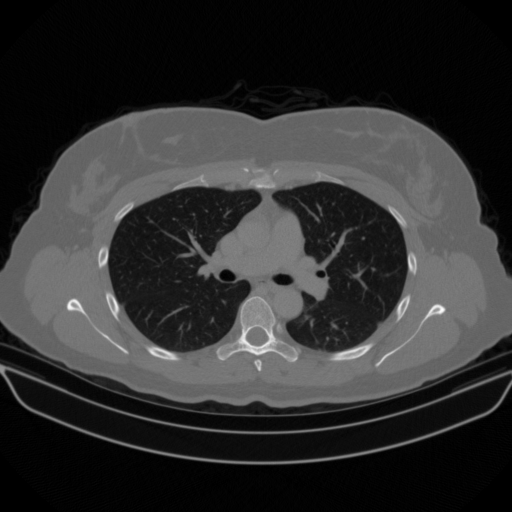

Slice 70 Targeting Evaluation

Slice: Slice_70

Slice Thickness: 1.5mm

Conversion: NATIVE β†’ VENOUS

Targeted Slice 70 - Lung Window Analysis (Generated vs Real Venous)

0.763

Lung SSIM

85.0

Lung RMSE

36.7

Lung MAE

Average Lung Window Metrics Across All Slices (170 slices) - Generated vs Real Venous

0.767

Lung SSIM (Avg)

89.5

Lung RMSE (Avg)

37.4

Lung MAE (Avg)

Generated VENOUS CT scan (A→B translation)

No window - Raw intensity values

Lung window (WL -600, WW 1500 β†’ Low βˆ’1350, High +150)